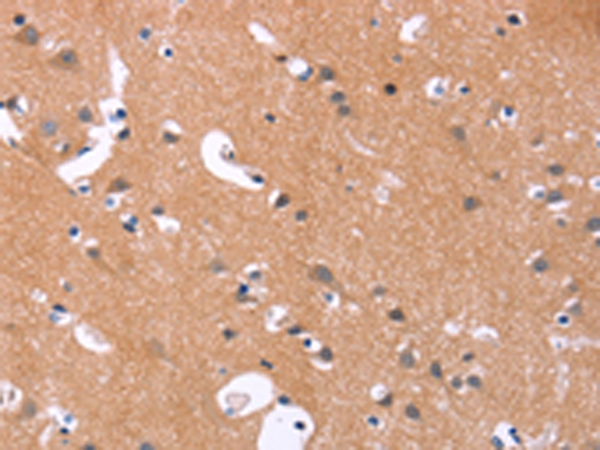

分类: 科研抗体货号: P04240别名: Fz2; fz-2; fzE2; hFz2应用: IHC反应种属: Human, Mouse, Rat